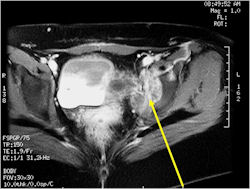

Radiographic Presentation

- Soft Tissue Mass in 90% of of cases

- Ewing sarcoma responds well to chemotherapy. Often there is a dramatic reduction in size of the tumor.

- Most common chemotherapy agents utilized include as of 2008: Vincristine, Adriamycin, Cyclophosphamide, Actinomycin-D, Ifosfamide, Etoposide

- Most protocols administer preoperative chemotherapy then surgery is performed. Surgery is followed by several courses of postoperative chemotherapy.